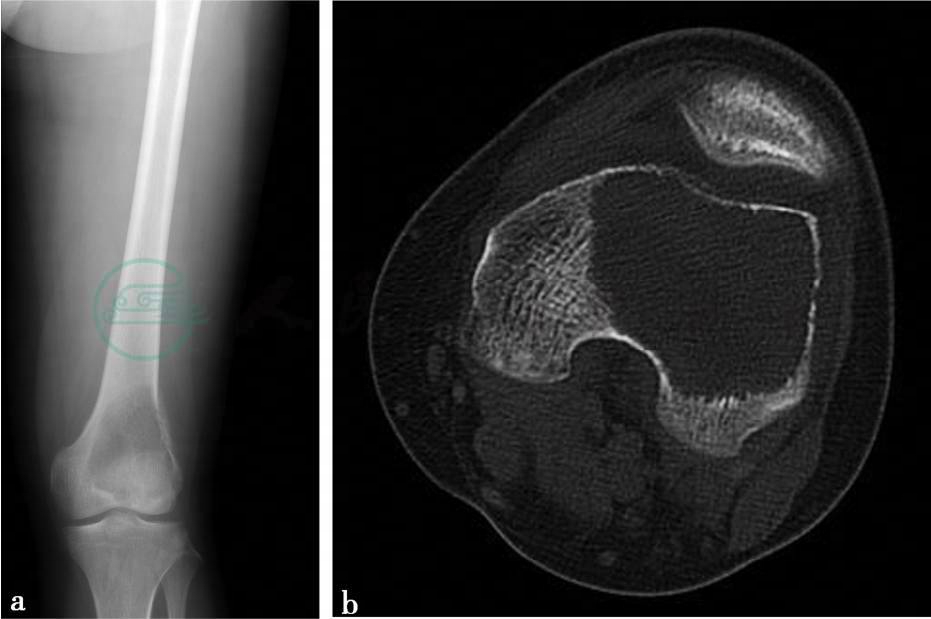

(1)病例1:

X线、CT平扫及MRI平扫。

图1 图1a,X线示左股骨远端可见偏向股骨外侧髁的偏心性骨质破坏,病灶大小约6.3cm×7.9cm,边缘较清楚,无硬化边。病灶位于股骨远端,越过骨骺线,直达关节面骨皮质下,受累骨皮质完整。无骨膜反应。周围软组织清晰,无异常表现。图1b~d,CT示左股骨远端偏心性骨质破坏,病灶大小约6.3cm×7.9cm,略成膨胀性改变,边缘较清楚,无硬化边,密度较均匀,CT值约30HU。外侧骨皮质部分缺损,病灶内组织通过破损的皮质向外侧略突出,无骨膜反应。图1e、f,MRI示左股骨远端膨胀性骨质破坏,边界较清楚,病灶组织向外侧略突出于皮质外。图1e,病灶在T1WI上呈低信号。图1f,在T2WI脂肪抑制像上呈略高信号,其内有多个圆形的更高囊状信号影,其中一个较大,无液-液平面。无明确骨膜反应表现